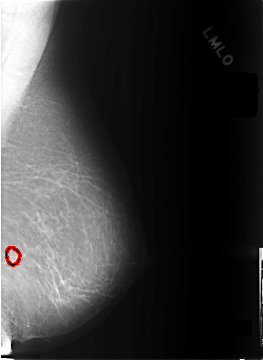

C_0301_1.LEFT_MLO

FILE: C_0301_1.LEFT_MLO.OVERLAY

TOTAL_ABNORMALITIES 1

ABNORMALITY 1

LESION_TYPE CALCIFICATION TYPE PLEOMORPHIC DISTRIBUTION CLUSTERED

ASSESSMENT 4

SUBTLETY 4

PATHOLOGY BENIGN

TOTAL_OUTLINES 1

BOUNDARY